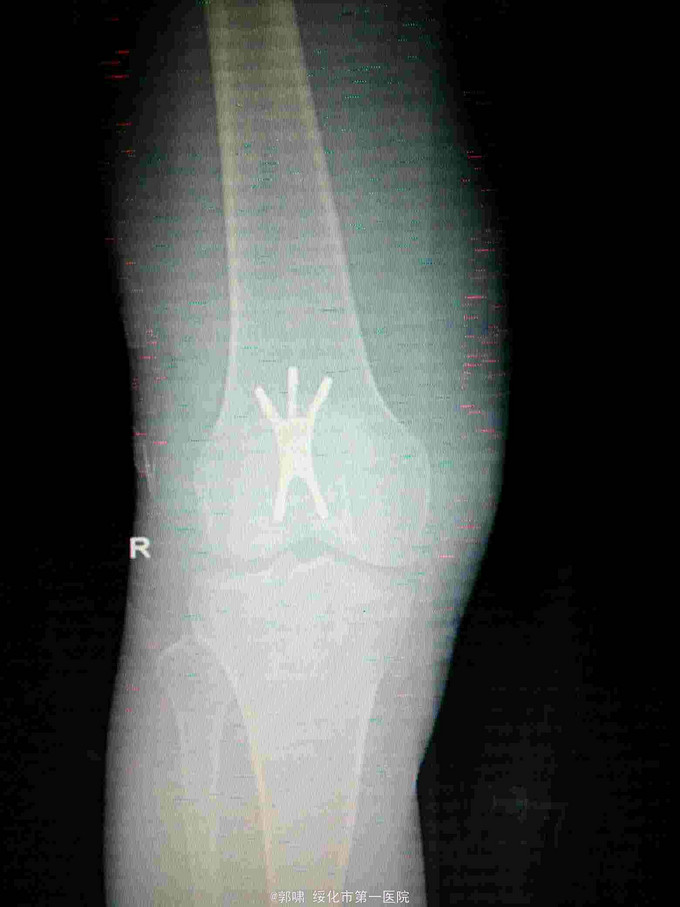

左膝关节摔伤,肿胀,畸形,活动受限一小时。收入院。患者于一小时前滑倒摔伤。当即倒地,左膝关节肿胀,畸形不能行走。门诊拍片示:左膝关节髌骨骨折,断端移位。门诊以左髌骨骨折收入院。

左膝关节肿胀,局部畸形,不能下地行走。浮髌试验阳性。拍片示:左髌骨骨折。

诊断:左髌骨骨折。立即予以腰麻下行切开复位内固定术。术中复位骨折,缝合筋膜,冰水浸泡髌骨爪约10分钟。待髌骨爪变软。选取合适大小的髌骨爪。应用记忆合金髌骨爪内固定。立即用40°温盐水热敷局部。使记忆合金加速抓紧。环抱。缝合爪齿二道,防止脱落。缝合关节囊,韧带组织。术毕。

应用记忆合金髌骨爪内固定髌骨骨折。手术时间基本在20----30分钟内都可以完成。局部损伤小。固定牢靠,确实。患者二个月就可以下地负重活动。具体手术技巧。一是髌骨爪提前用冰盐水侵泡10分钟左右。待记忆合金变软即可使用。二。固定牢靠后立即用40°温盐水热敷。使其快速抓紧。三,缝合爪齿,防脱。四如有粉碎,小的骨块可以缝合筋膜固定。有大骨块,最好环扎钢丝,或穿针固定,有时穿骨隧道钢丝捆扎。效果也不错。只要做到以上几点。安全无忧了!以下是以前做的片子。可以看一看。